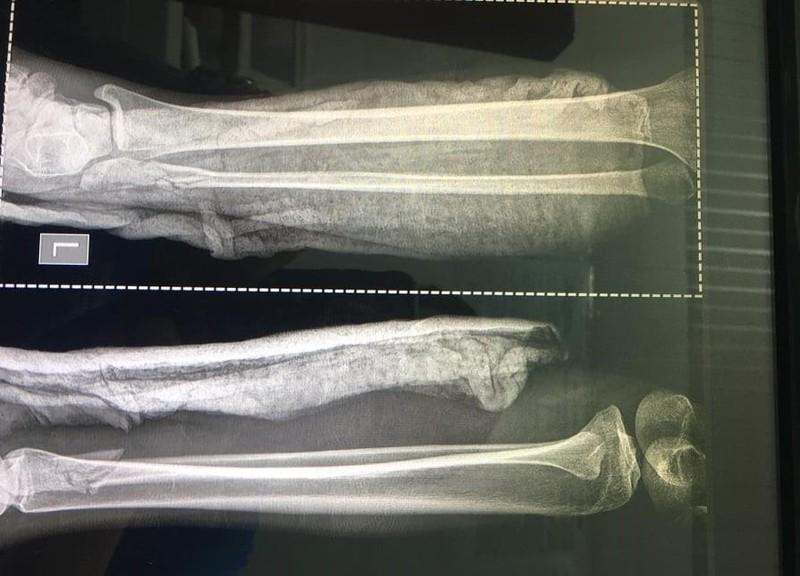

Theo BV Chợ Rẫy, bệnh nhân bị chấn thương đầu, vỡ nền sọ (gãy xoang sàng hai bên); cả tay trái và phải bị gãy xương trụ, xương quay, xương mác; gãy nhiều xương ngón tay ở bàn tay trái… Đặc biệt nạn nhân đang có thai sống khoảng 26 tuần.

Cả tay và chân nạn nhân đều bị gãy.